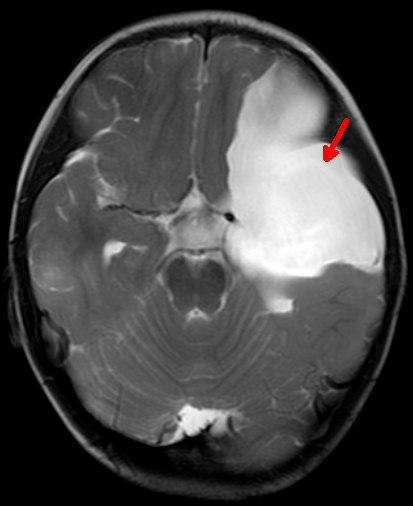

2岁的浩浩(化名)是个可爱男宝宝。一个月前家人发现他间断恶心、呕吐,在当地医院查了个头部的CT,结果显示浩浩左侧接近一半的脑子被一个巨大“水球”所占据,医学上叫做“中颅窝蛛网膜囊肿”。由于孩子太小,家人很是谨慎,经过多方打听了解到郑州大学五附院有神经内镜治疗颅内蛛网膜囊肿技术,于是转入神经外科三病区就诊。浩浩的病情得到了付旭东主任和麻醉科胡强夫主任及其团队的高度重视,为其制定了周密的手术方案,同样要把“死水”变成“活水”。在兄弟科室的通力合作下手术过程顺利,术后浩浩的症状明显改善,家人悬着的一颗心也终于落了地。同样由于神经内镜创伤小的优点,浩浩很快顺利康复出院。

术后11天复查MRI囊肿明显缩小,脑组织回弹